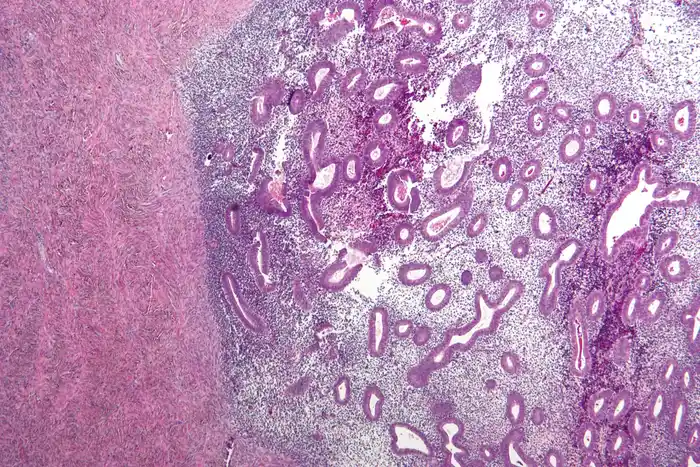

Micrografia de endometriose do ovário corada por hematoxilina e eosina.

Nephron · CC BY-SA 3.0